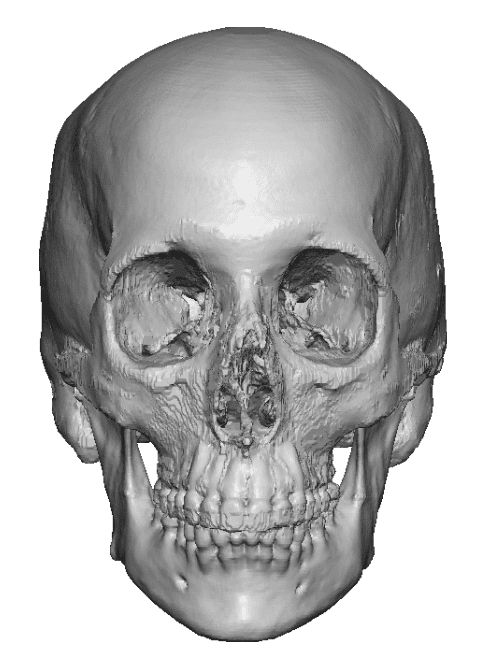

Severe narrowing skull deformity from prior sagittal craniosynostosis repair as an adult.

Complete replacement of entire skull by a custom implant with temporal fat injections.